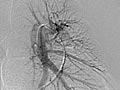

Angiogram of the Lung

An angiogram of the lung is an X-ray test that uses a special dye and camera (fluoroscopy) to take pictures of the blood flow in the blood vessels of the lung.

A lung (pulmonary) angiogram is used to check the arteries that lead to the lungs (pulmonary arteries) and the blood vessels in the lungs. It can also find narrowing or a blockage in a blood vessel that slows or stops blood flow.

Normal:

The dye flows evenly through the blood vessels.

No narrowing, blockage, bulging, or other problem of the blood vessels is seen. The pulmonary artery pressures are normal.